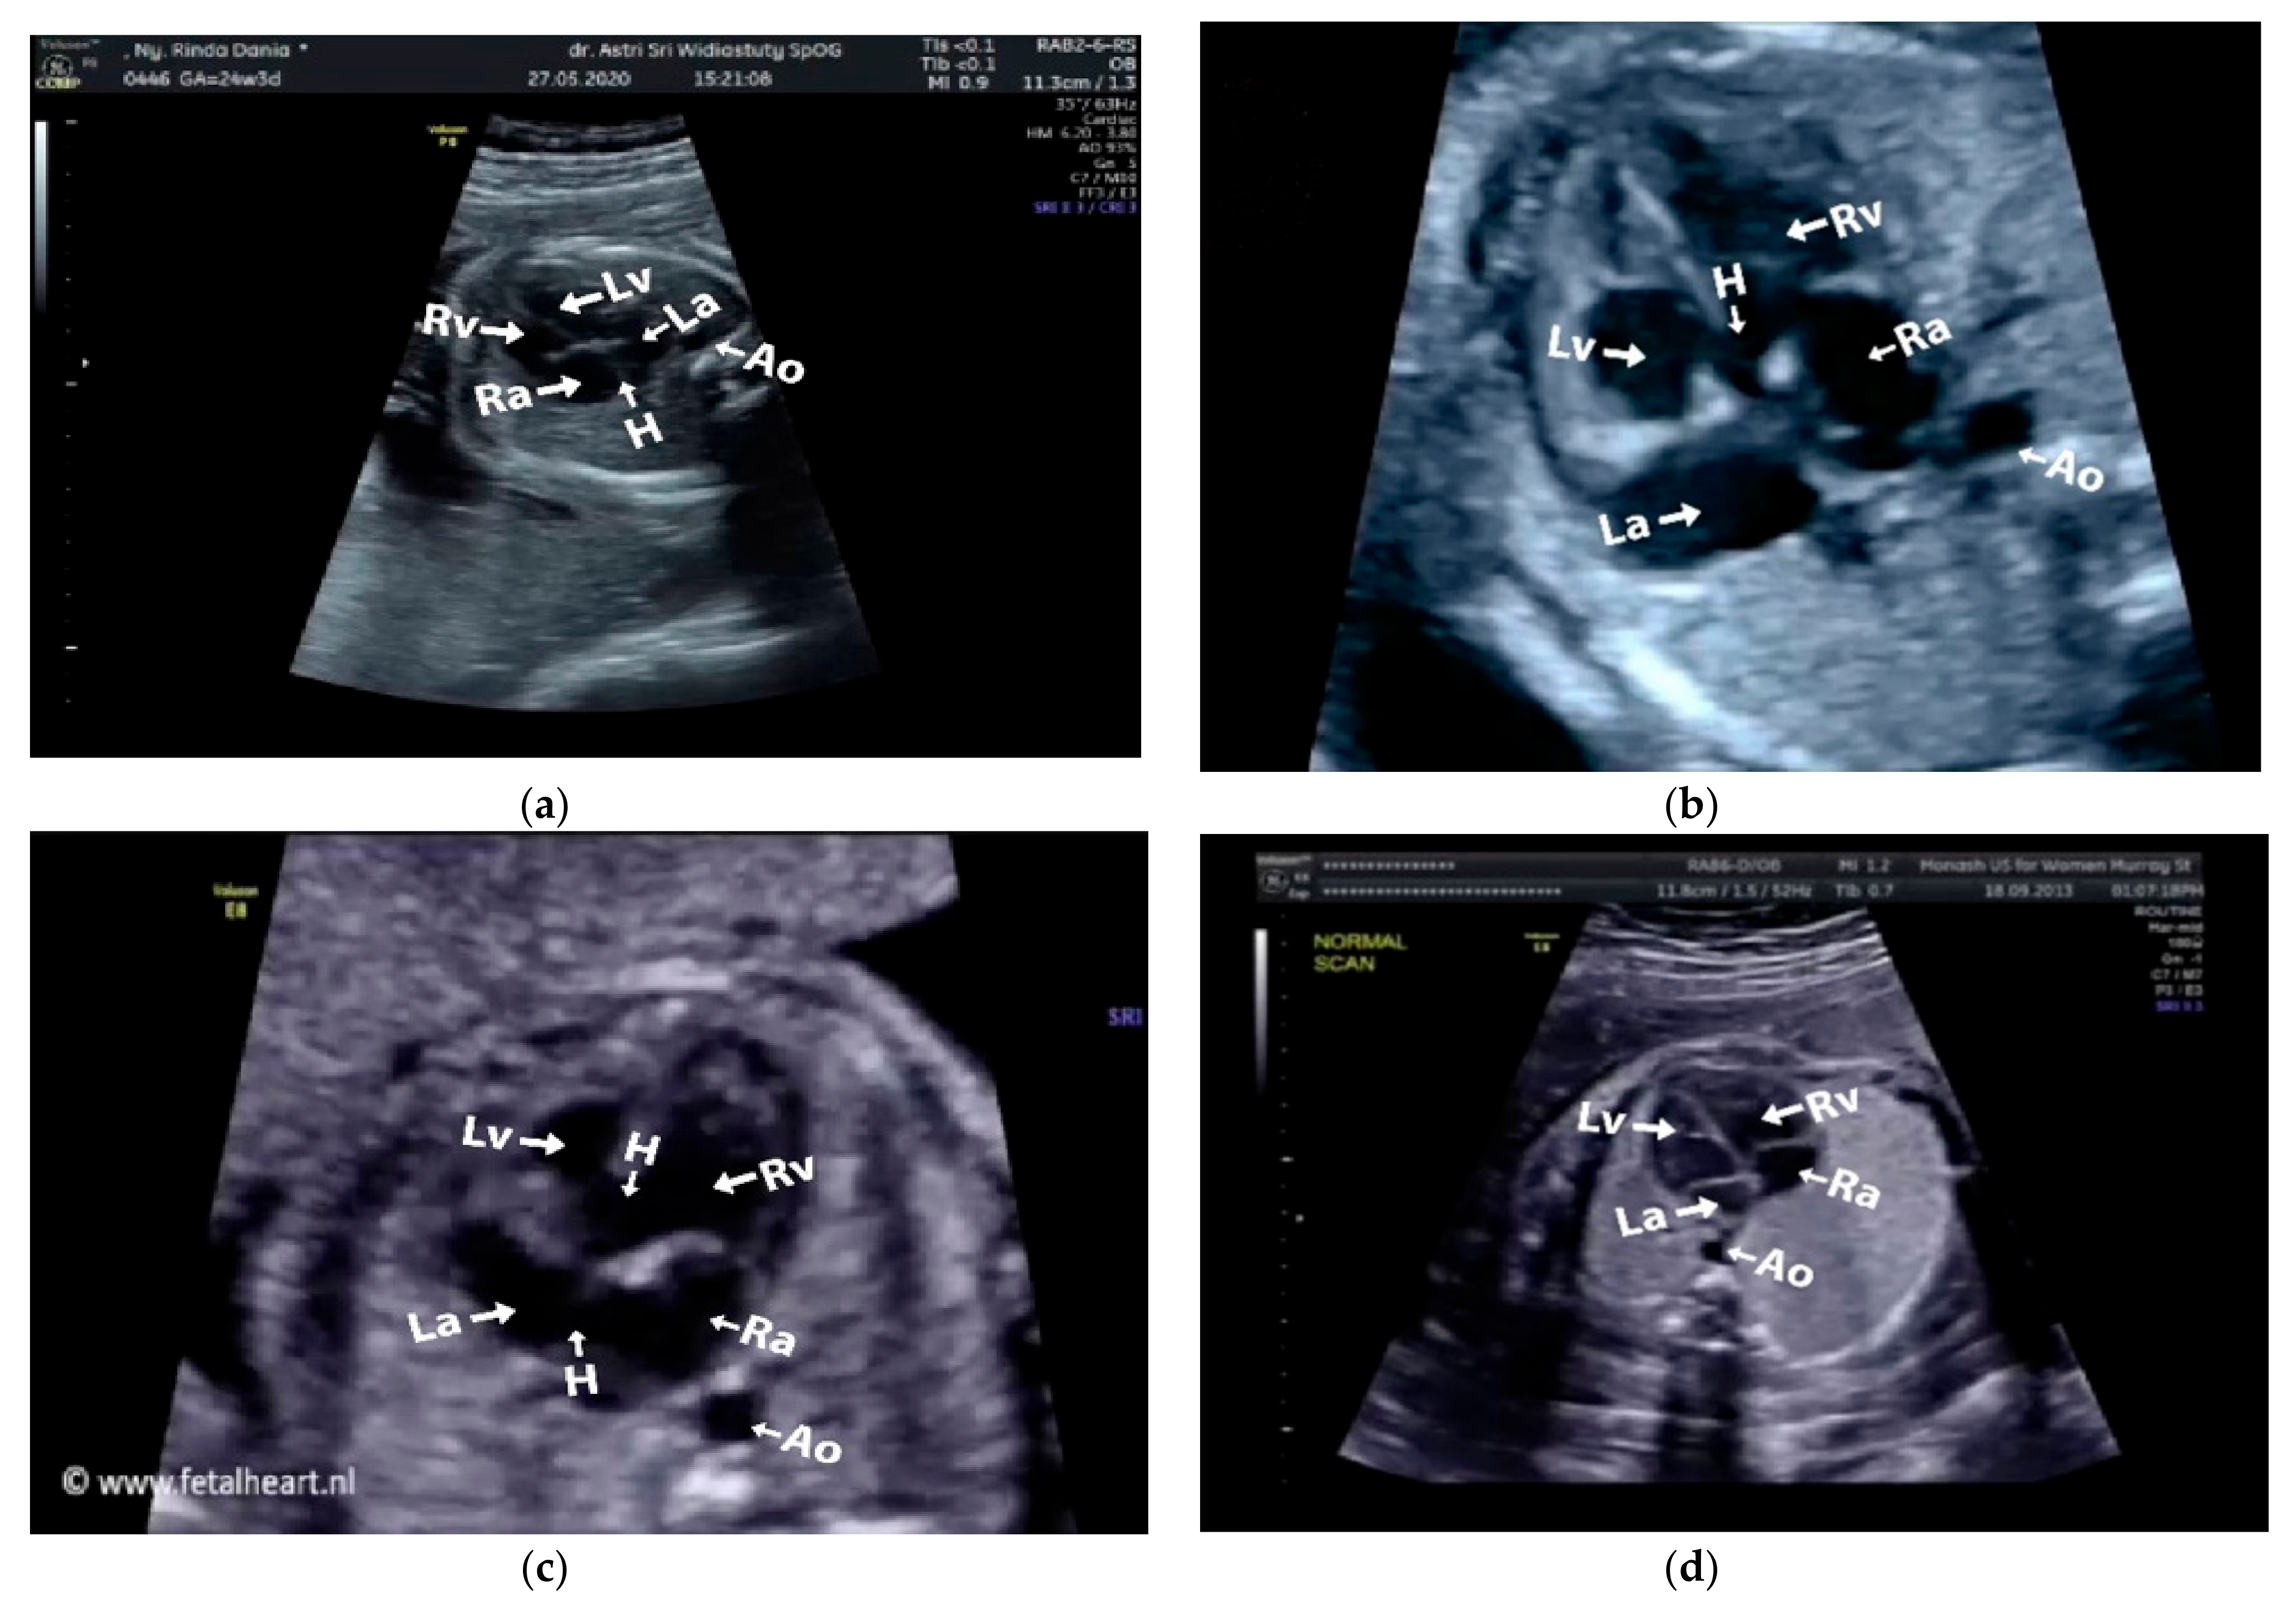

Images with inappropriate anatomical planes (cropped or badly captured) and those with calipers were excluded. The dataset composition was clearly imbalanced (some classes were more frequent than others), as is usually the case in real clinical scenarios. The sample of the raw ultrasound image was based on four views in normal anatomy, as depicted in Figure 2. In such sample, there are the left atrium (LA), left ventricle (LV), right atrium (RA), right ventricle (RV), ductus arteriosus (DUCT), superior vena cava (SVC), aorta ascendens (AoA), aorta descendens (Ao), and main pulmonary artery (MPA), whereas the sample of the raw ultrasound image of abnormal anatomy structure, with the three heart defects such as ASD, VSD, and AVSD condition, is compared to normal anatomy structure in Figure 3. In the abnormal structure, there are hole (H) as heart defect in each condition. Each defect has the variation of hole size; such hole size indicates the disease severity. However, in this study, we only detected the hole, without measuring the hole size.

Figure 3.

Fetal heart scan in 4CH view for CHDs detection: (a) ASD; (b) VSD; (c) AVSD; and (d) Normal.

Especially for heart defect detection, only 4CH view was used to analyze ASD, VSD, and AVSD images. Annotated images indicate the position of defect in the atrium, ventricle, or both of them. Figure 4 depicts the sample of annotated images for a standard view of 4CH, 3VT, LVOT, and RVOT, and Figure 5 shows the sample annotated images of defect position in ASD, VSD, and AVSD. Finally, the whole annotated images are labelled as the ground truth database, and it was saved in the JSON file format (json).

Figure 4.

The sample of annotated images by maternal–fetal clinician for standard fetal heart view segmentation in (a) 4CH (orange: view, cyan: AoA, red: LA, grey: RA, green: LV, and red: RV); (b) LVOT (orange: view, cyan: LA, purple: RV, and blue: LV); (c) RVOT (orange: view, green: MPA, red: DUCT, and yellow: SVC); and (d) 3VT (purple: view, yellow: AoA, green: SVC, and red: DUCT); based on normal anatomy.

Figure 5.

The sample of annotated image by maternal–fetal clinician for heart defect detection in case: (a) ASD; (b) VSD; and (c) AVSD. In the annotation, the green line is RA, the red line is LA, the purple line is RV, the blue line is LV, and the yellow line is defect.